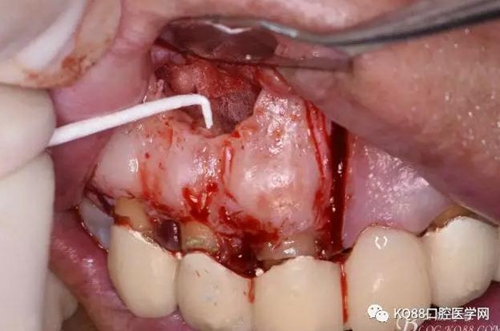

圖8.翻開梯形瓣

圖9.去除唇側(cè)薄的骨壁,暴露出囊壁

圖10.剝離囊壁